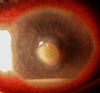

Results: Primary interface complications include infectious keratitis, diffuse lamellar keratitis, central toxic keratopathy, pressure-induced stromal keratopathy (PISK), and epithelial ingrowth. Infectious keratitis is most commonly caused by Methicillin-resistant Staphylococcus aureus (early onset) or atypical Mycobacterium (late onset) postoperatively, and immediate treatment includes flap lift and irrigation, cultures, and initiation of broad-spectrum topical antibiotics, with possible flap amputation for recalcitrant cases. Diffuse lamellar keratitis is a white blood cell infiltrate that appears within the first 5 days postoperatively and is acutely responsive to aggressive topical and oral steroid use in the early stages, but may require flap lift and irrigation to prevent flap necrosis if inflammation worsens. In contrast, PISK is caused by acute steroid response and resolves only with cessation of steroid use and intraocular pressure lowering. Without appropriate therapy PISK can result in severe optic nerve damage. Central toxic keratopathy mimics stage 4 diffuse lamellar keratitis, but occurs early in the postoperative period and is noninflammatory. Observation is the only effective treatment, and flap lift is usually not warranted. Epithelial ingrowth is easily distinguishable from other interface complications and may be self-limited or require flap lift to treat irregular astigmatism and prevent flap melt.